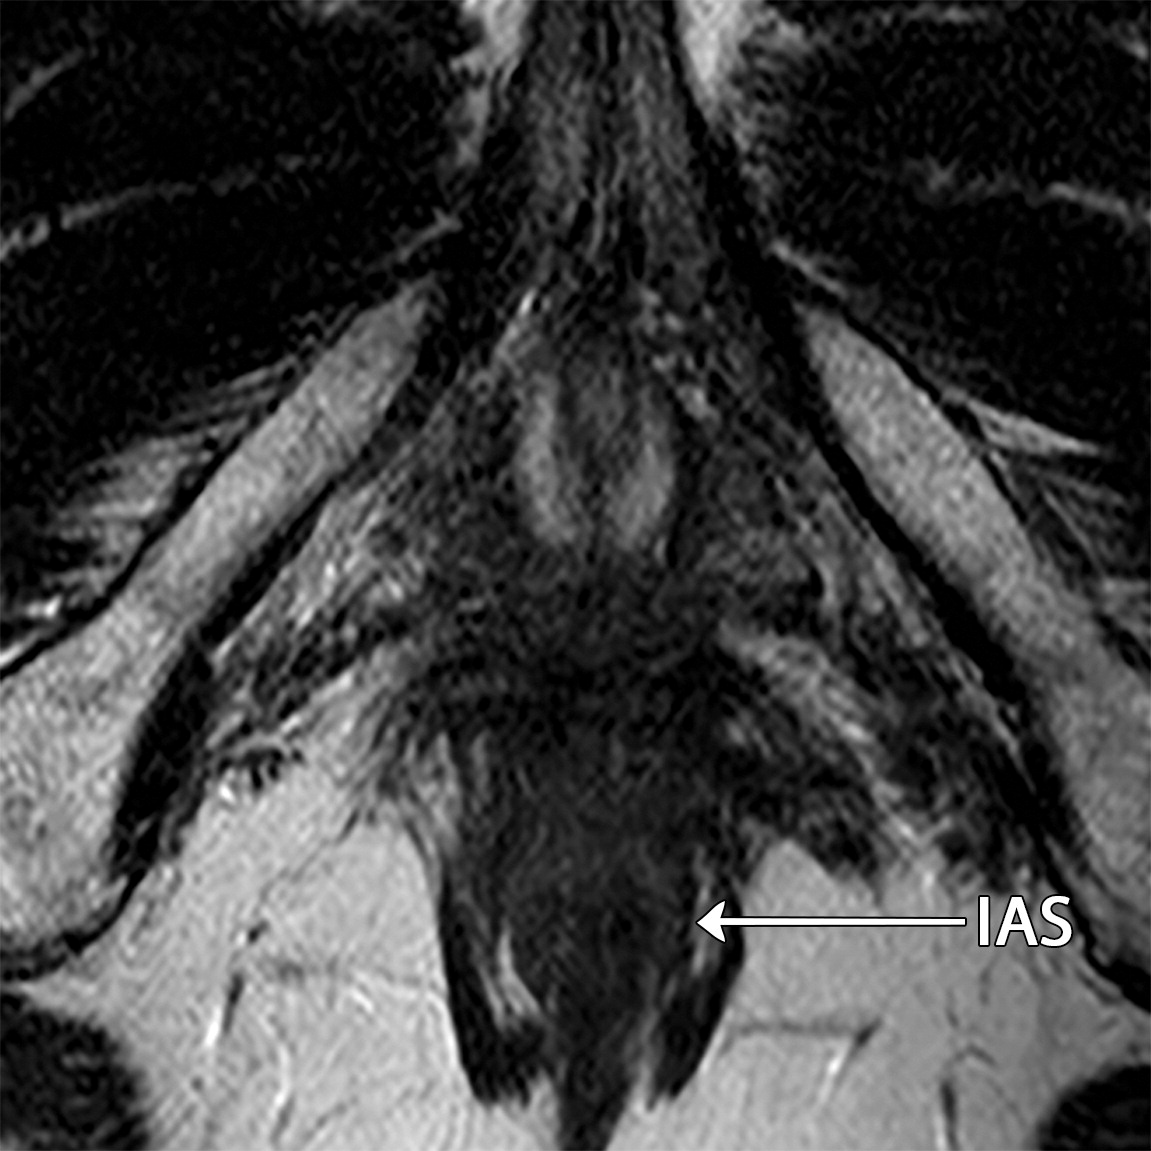

50岁以上男性骨盆和盆底的MRI解剖。

提肛肌(LA),由耻骨直肠肌(PR)、耻骨尾骨肌(PC)和髂尾骨肌(IC)组成;尾骨肌(C),前列腺(P),闭孔内肌(OI),会阴浅横肌(STP),球海绵体肌 (B), 坐骨海绵体肌(ISC),肛门外括约肌(EAS),肛门内括约肌(IAS),直肠(R),尿道括约肌(SU),也称为尿道外括约肌(U),它包围着整个膜性尿道。6774449af17bb1b8df6e83ab4e9fa158.jpeg